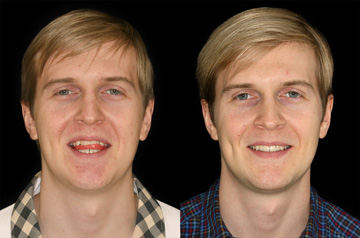

Face and Bite Correction

Primary Diagnoses

- Open bite

- Relapse after orthodontic treatment

Surgical solution

- Upper Jaw Osteotomy

- Lower Jaw Osteotomy

- Airway and Bite Correction

Surgery was performed in 2016 at our Face Smile Center by Dr. Andrey Senyuk, oral and maxillofacial surgeon.